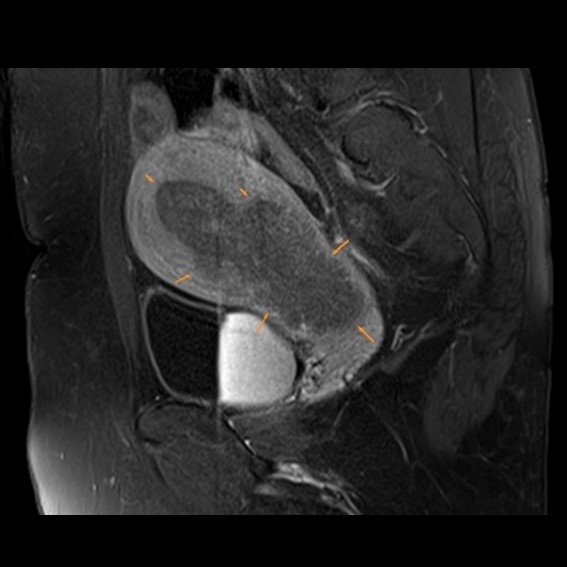

運用高科技尖端影像設備,提供貴賓精準的檢查、判讀、即時醫療、後續追蹤、健康管理或醫學中心轉介服務;從健檢診斷到後端治療,一條龍式服務。永越自成立以來,已服務超過16萬人次,每年通報件數超過千件,揪出包括:甲狀腺癌、肝腫瘤、肺癌、乳癌、子宮頸癌等重大異常的健康警訊,把握住早發現早治療的黃金關鍵。